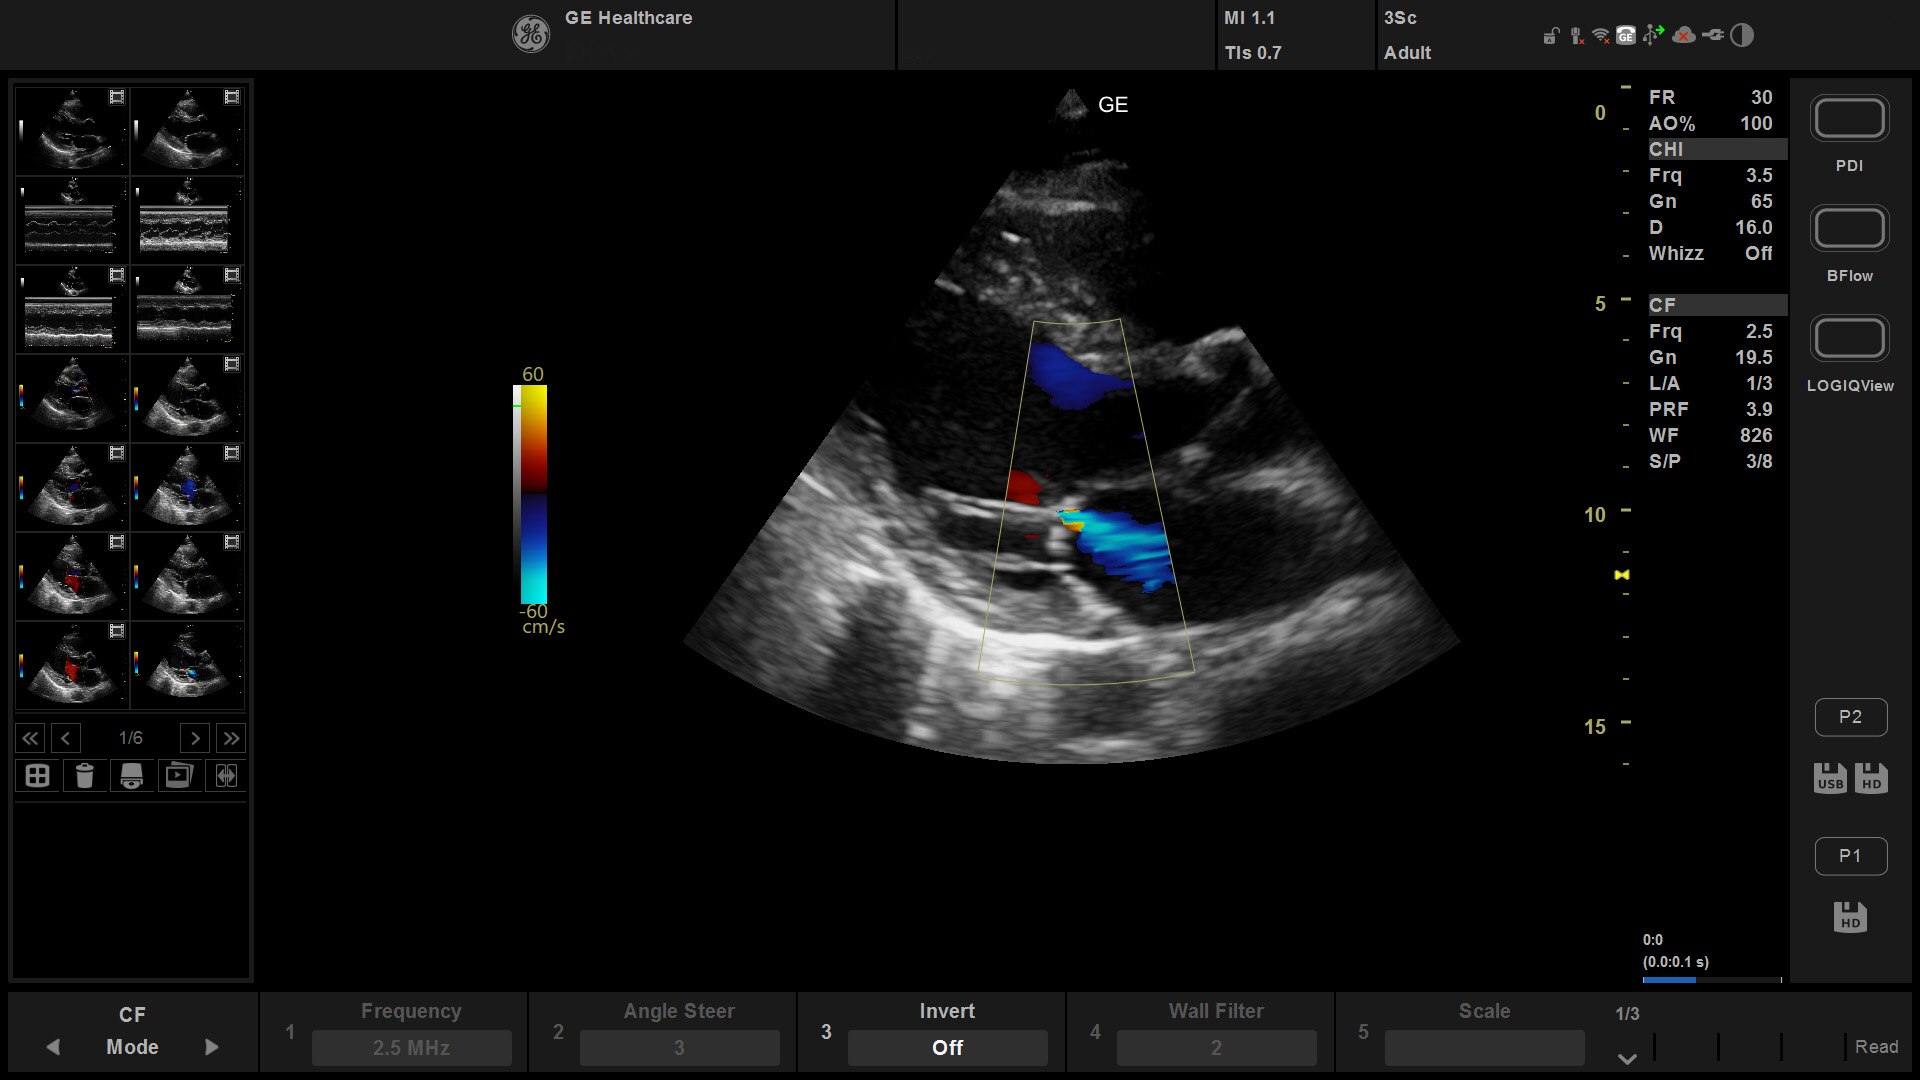

Automated Function Imaging

Quickly and easily assess structural heart defects.

Perform objective quantitative analysis of the complete longitudinal myocardial strain of the left ventricle, right ventricle and left atrium throughout the heart cycle. Once you obtain the specific images you need, the AFI measurement tool takes less than three minutes.³

CEUS

Evaluate a variety of conditions at the bedside.

Constrast-Enhanced Ultrasound (CEUS) lets you evalute conditions such as abdominal solid organ injuries, lacerations, hematomas, lesions, tumors and active bleeding. CEUS also supports cardiac assessment of the LVEF, regional Wall motion and structural abnormalities.